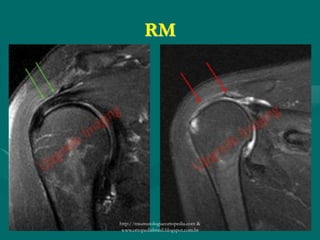

RM

- Alta sensibilidade e especificidade >90%;

- Preferencialmente contraste;

.Gadolínio

- Útil na fase inflamatória e na ruptura (extensão da

lesão e retrações);

- Detecção da degeneração gordurosa;http://traumatologiaeortopedia.com &